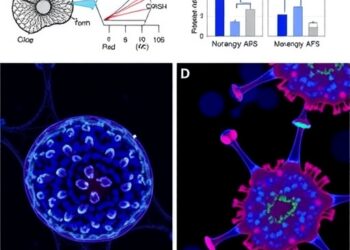

Photoimmunotherapy Targets CD98 in Solid Tumors

In a groundbreaking advance in cancer treatment, researchers have unveiled the promising therapeutic potential of photoimmunotherapy targeting solid tumors expressing...